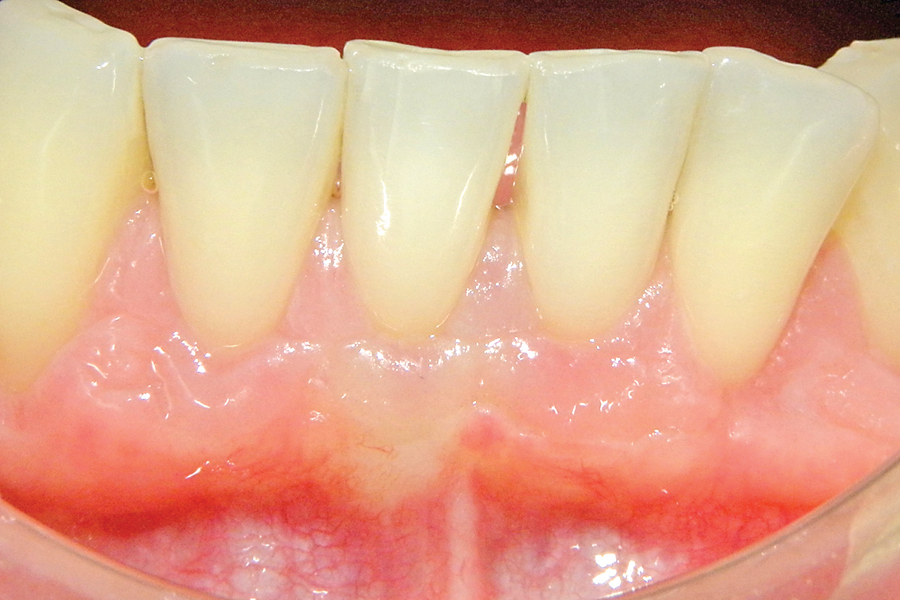

Food Choices For Optimal Post-Operative Healing: What Advice Can We Provide a Patient?

The success of a delicate periodontal procedure is dependent on both the skill of the clinician as well as several patient-associated factors. These include the past and present smoking status, systemic health conditions and compliance to post-operative protocols. Any one of the factors or in combination can delay or impair the healing process. However, common … Read more